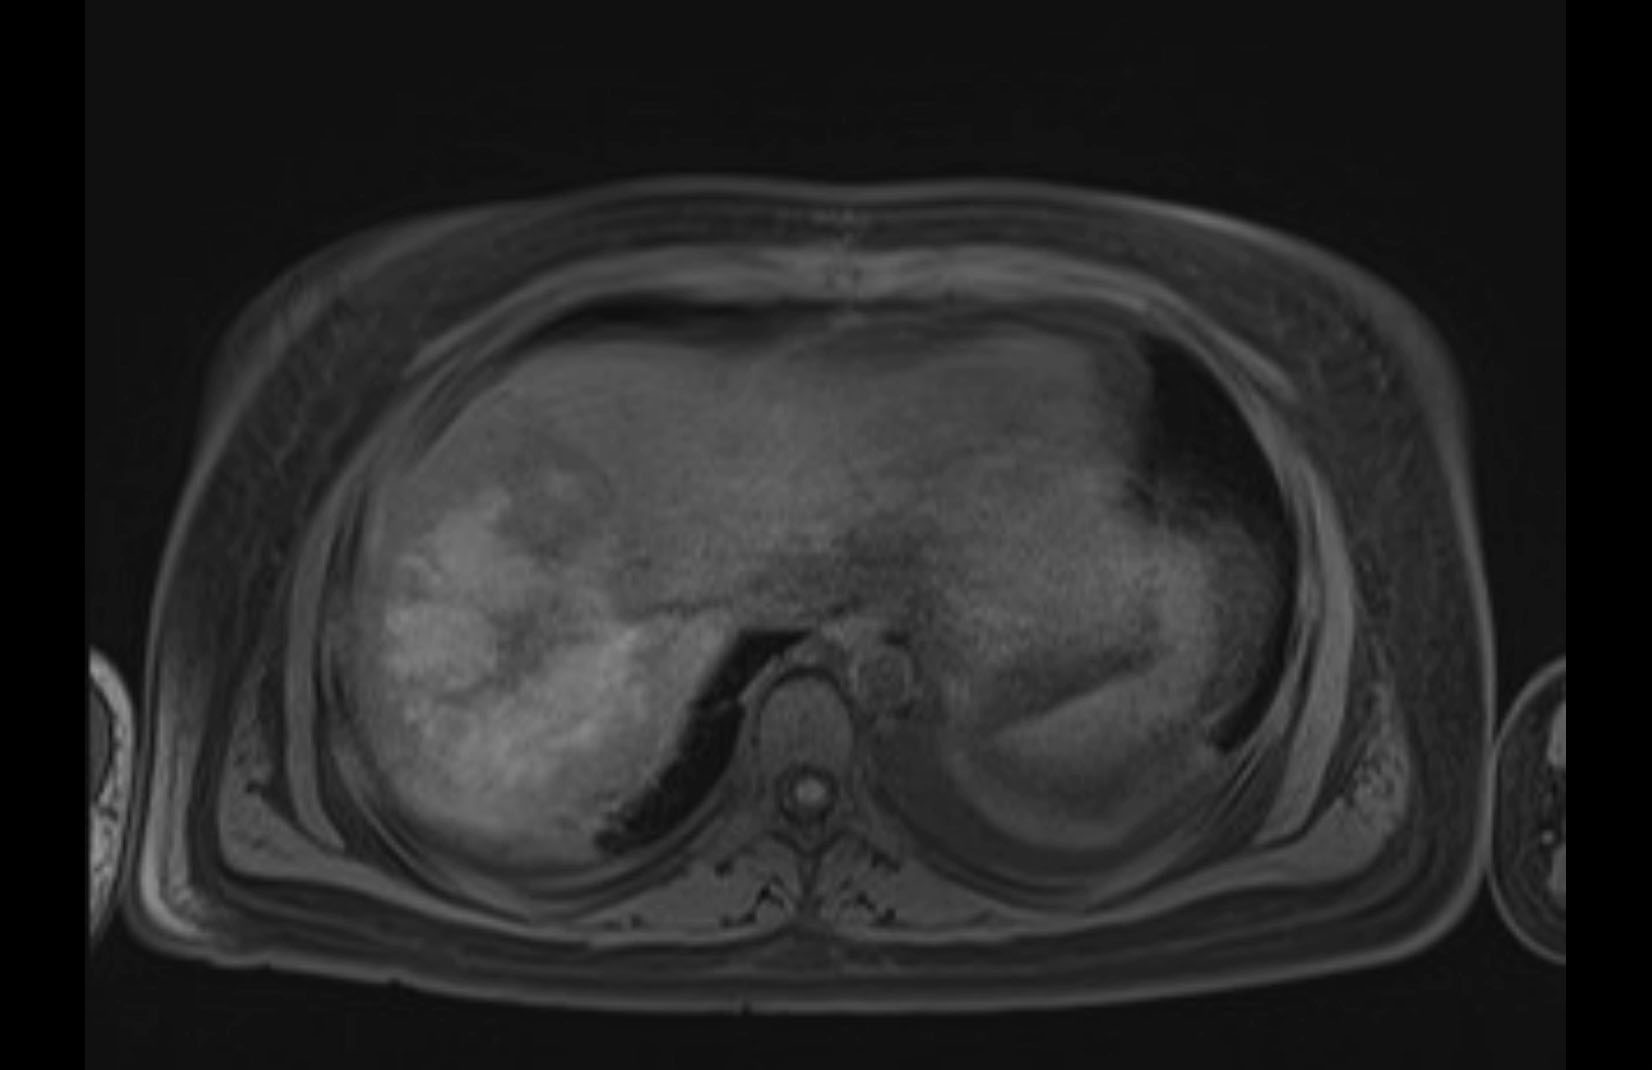

Imaging Analysis

Look through the patient's CT scan to identify any areas of concern for the necessary procedure.

MRI T1

MRI T2

Based on initial findings, which issue(s) would you be most concerned about?